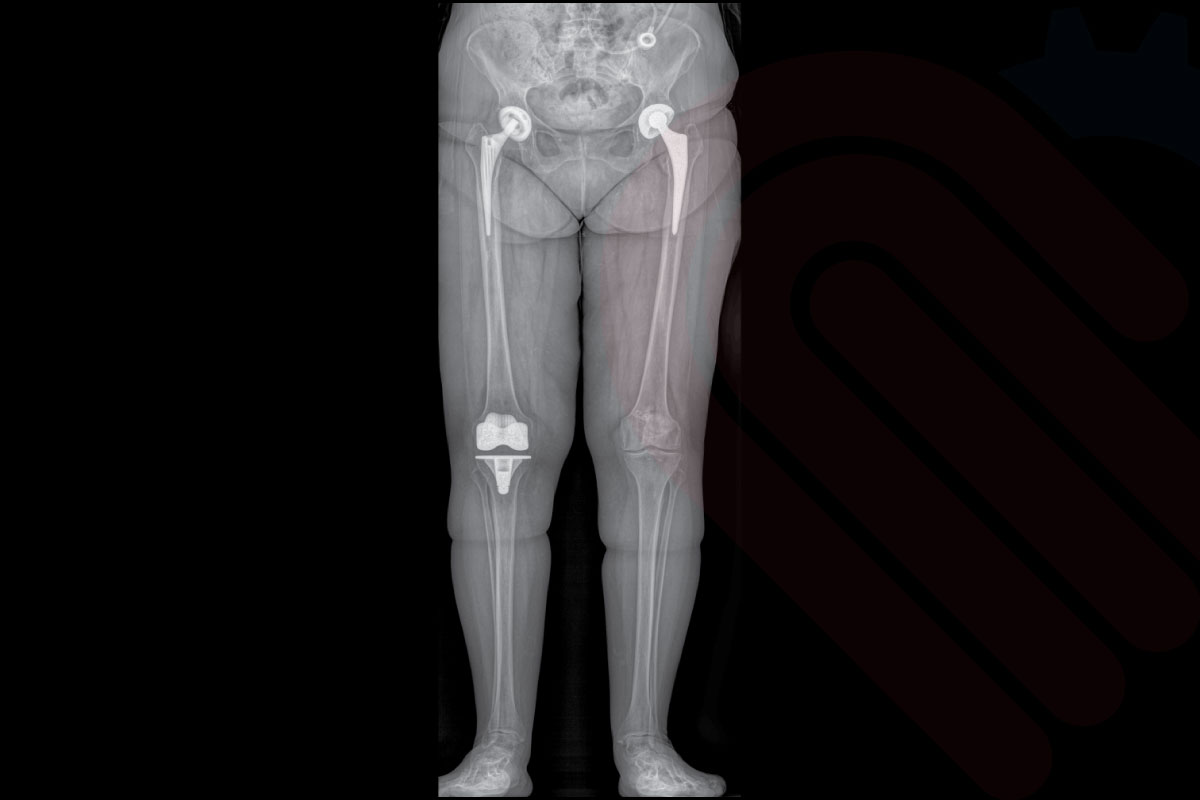

kneeEOS, EOSedge sistemi ile elde edilen düşük doz, gerçek boyutlu biplanar görüntülerden faydalanarak alt ekstremite hizalanmasının 3D analizini ve cerrahi planlamasını yapan özel bir yazılımdır. Total diz protezi (TKA) ve diğer diz rekonstrüksiyon cerrahilerinde, mekanik eksen hizalaması, kemik kesim açıları ve implant boyutlandırması gibi kritik parametreleri preoperatif olarak belirlemenizi sağlar. Hastanın yük taşıyan pozisyonda çekilmiş görüntüleri sayesinde, planlamalar fizyolojik yük koşullarına uygun şekilde yapılır. Klinik araştırmalar, kneeEOS ile yapılan planlamaların, cerrahi sonrası mekanik eksen doğruluğunu ve implant yerleşim hassasiyetini anlamlı ölçüde artırdığını ortaya koymuştur*.

Klinik Destek

• Parratte et al., The Journal of Arthroplasty, 2018

• → kneeEOS planlaması ile yapılan TKA cerrahilerinde, postoperatif mekanik eksen hizalanması doğruluğu anlamlı derecede artmıştır.

hipEOS, EOSedge sistemi ile elde edilen düşük doz, gerçek boyutlu biplanar görüntüler üzerinden kalça ekleminin 3D analizini ve cerrahi planlamasını yapan gelişmiş bir yazılımdır. Total kalça protezi (THA) ve diğer kalça rekonstrüksiyon cerrahilerinde, asetabular kupa açısı, femoral stem pozisyonu, bacak uzunluğu farkı ve offset gibi kritik parametreleri preoperatif olarak belirlemenize olanak tanır. Yük taşıyan pozisyonda elde edilen görüntüler sayesinde, implant yerleşimi ve pozisyonlaması hastanın doğal biyomekaniğine en uygun şekilde planlanabilir. Klinik veriler, hipEOS planlaması ile gerçekleştirilen operasyonlarda postoperatif bacak uzunluğu eşitliği ve komponent pozisyon doğruluğunda anlamlı iyileşmeler olduğunu göstermektedir*.

• Sariali et al., Clinical Orthopaedics and Related Research, 2012

→ hipEOS planlaması ile yapılan THA cerrahilerinde asetabular komponent yerleşim doğruluğu ve bacak uzunluğu eşitliği anlamlı düzeyde artmıştır.